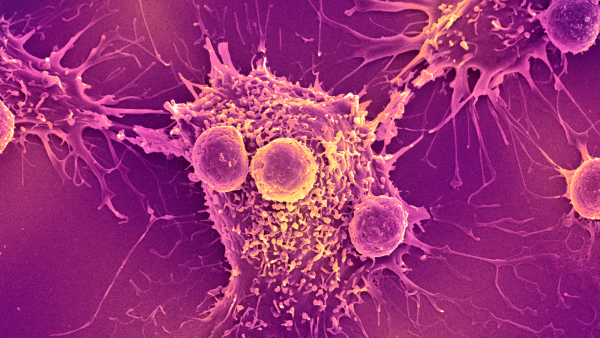

Після введення людського естрогену миші почали виробляти безліч людських імунних клітин. Серед них були Т-клітини, які безпосередньо атакують мікроби, та В-клітини, що виробляють антитіла, що знищують бактерії та допомагають позначити патогени для знищення.

Щоб побачити, як гуманізовані миші реагують на вакцину, команда ввела тваринам вакцину проти COVID-19, виготовлену компанією Pfizer-BioNTech. У відповідь миші виробили людські антитіла проти коронавірусу SARS-CoV-2. Аналогічно, під час впливу білків бактерії Salmonella typhi, збудника черевного тифу, миші виробляли антитіла проти збудника.

За його словами, мишей також можна використовувати для розробки нових методів лікування, які працюють шляхом зміни активності імунної системи, таких як інгібітори контрольних точок для раку. Ці препарати допомагають імунній системі краще націлюватися на ракові клітини для знищення.